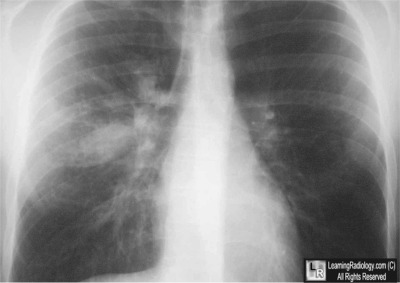

Frontal Radiograph of Chest

5. Allergic Bronchopulmonary Aspergillosis

Allergic Bronchopulmonary Aspergillosis

- Inflammation of the airways caused by an allergic response to Aspergillus Fumigatus

- Associated in 2% of cases with asthma and in 10% of cases of cystic fibrosis

- Most common in 3rd-4th decades of life

- Repeated episodes of inflammation and obstruction lead to bronchiectasis